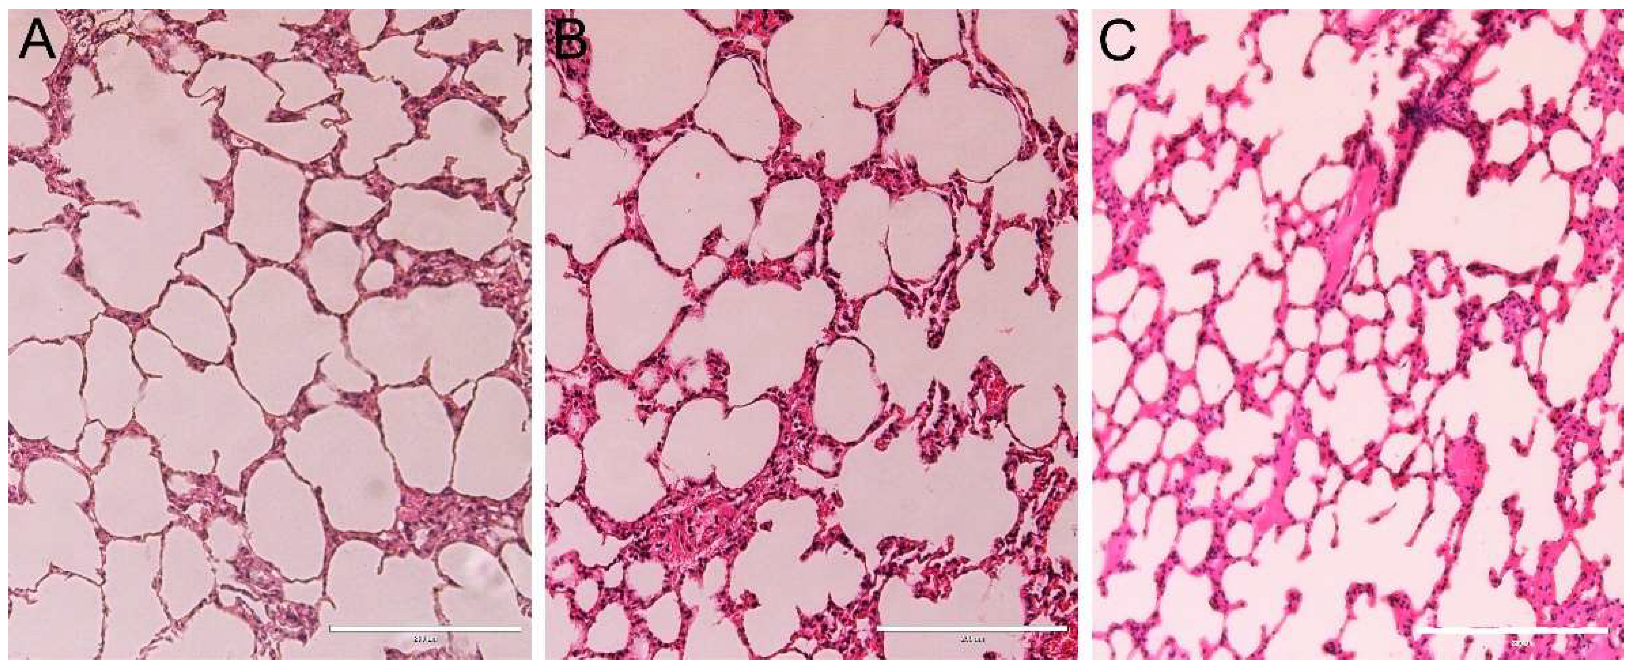

2.7. Organ Micro-Computed Tomography (Micro-CT) and Histological Analysis

3.7. Histopathology